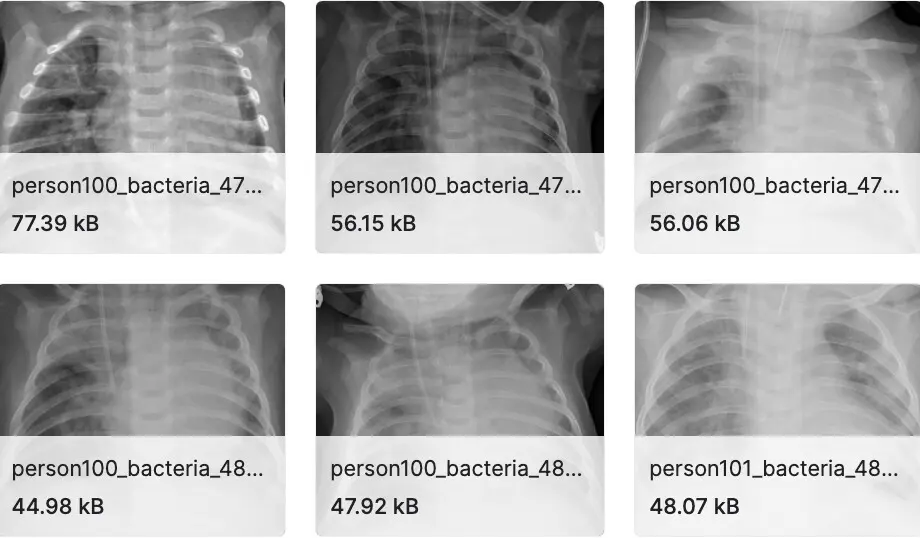

胸部 X 光图像(肺炎)

数据集分为 3 个文件夹(train、test、val)并包含每个图像类别(肺炎/正常)的子文件夹。有 5,863 张 X 射线图像 (JPEG) 和 2 个类别(肺炎/正常)。胸部 X 光图像(前后位)选自广州市妇女儿童医疗中心 1 至 5 岁儿科患者的回顾性队列。